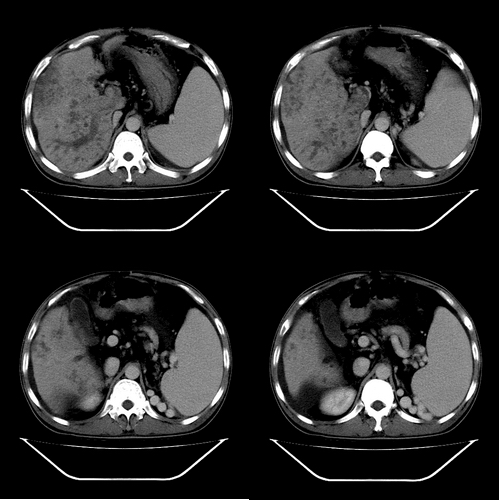

以下是引用yz在2006-6-2 12:20:00的发言:[br]肝左右叶比例失调,左叶体积明显缩小,肝边缘凹凸不平呈波浪状外观,肝左右叶可见不规则之斑片状低密度影,边界不清,以右叶为甚,肝门区增宽,增强后于动脉期病灶不均匀强化,门脉及延迟期均呈低密度,门脉主干及其右支无强化,以门脉右支明显,其内可见低密度影充填,门脉主干周围可见强化的细小侧支循环血管影。脾大,脾门血管明显增粗,脾后左侧膈脚前可见串珠状增粗强化血管影,并见胸腹水征。[br]1、考虑为弥漫性肝癌并肝门静脉主干及其右支癌栓形成,门脉海绵化。[br]2、肝硬化,脾大并门脉高压。[br]3、双侧少量胸水、腹水。